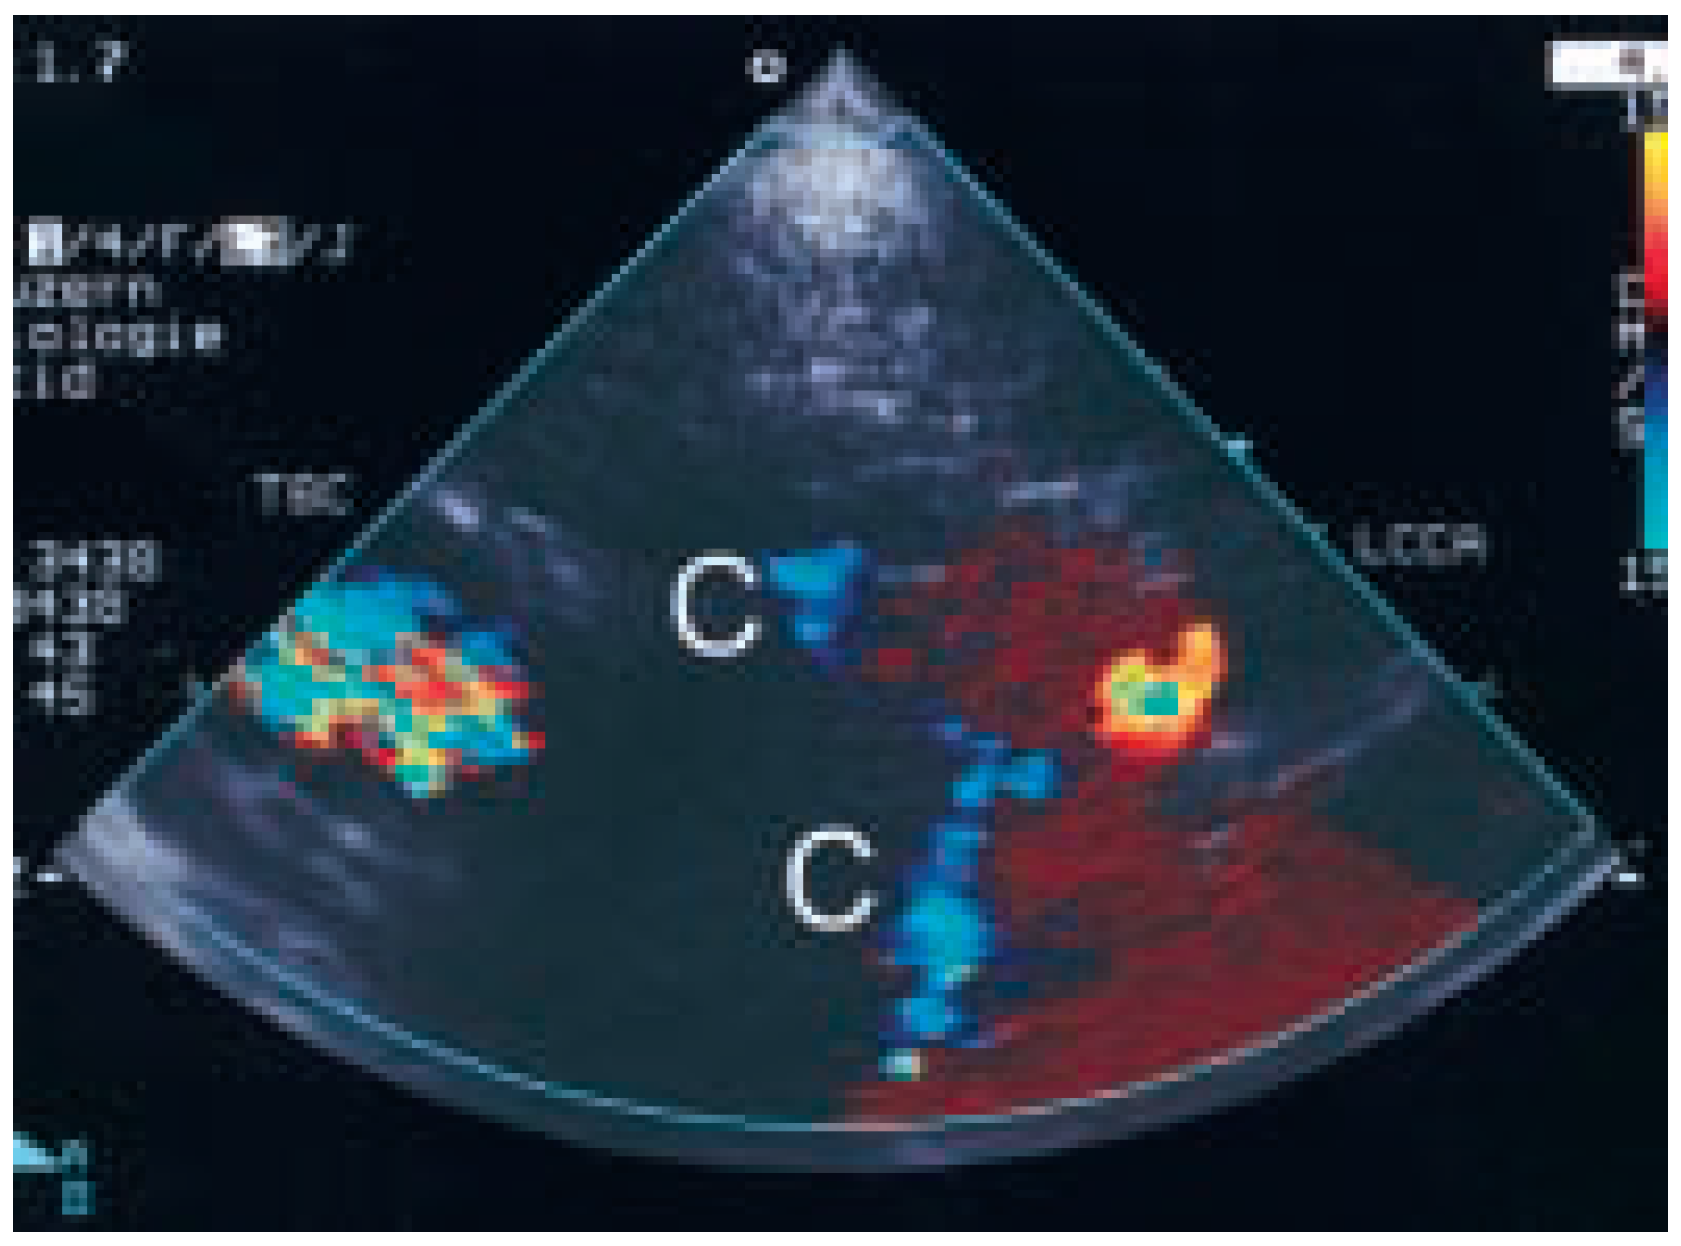

Persistent Elevated Jugular Venous Pressure and Pleural Effusion Following Myoardial Infarction

Case Report